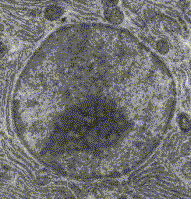

Organismos Eucariotas.

(multicelulares)